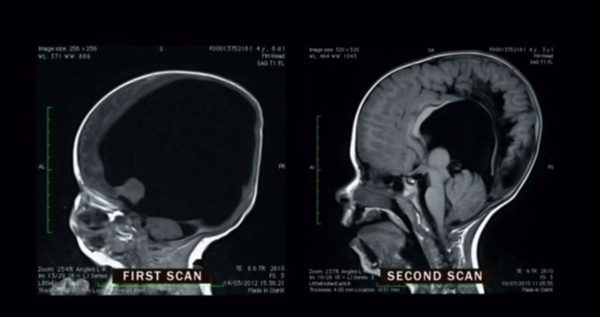

Bir süre sonra Noah adını verdikleri bebekleri dünyaya geldi. Ancak doktorların tahmin ettiği gibi beyni gelişmemişti. Minik bebek hemen yoğun bakım ünitesine kaldırıldı.

Uzun bir süre sonra mucize gerçekleşti. Noah’ın beyni hızla gelişmeye başladı. Yaşıtlarına oranla beyin gelişimi yavaş olsa da tahmin edilenlere göre çok hızlı bir gelişmeydi bu. Artık o da diğer çocukların yaptıklarını yapabilecekti. Dört yaşına geldiğinde ise yaşıtlarıyla arasında hiçbir fark kalmadı.